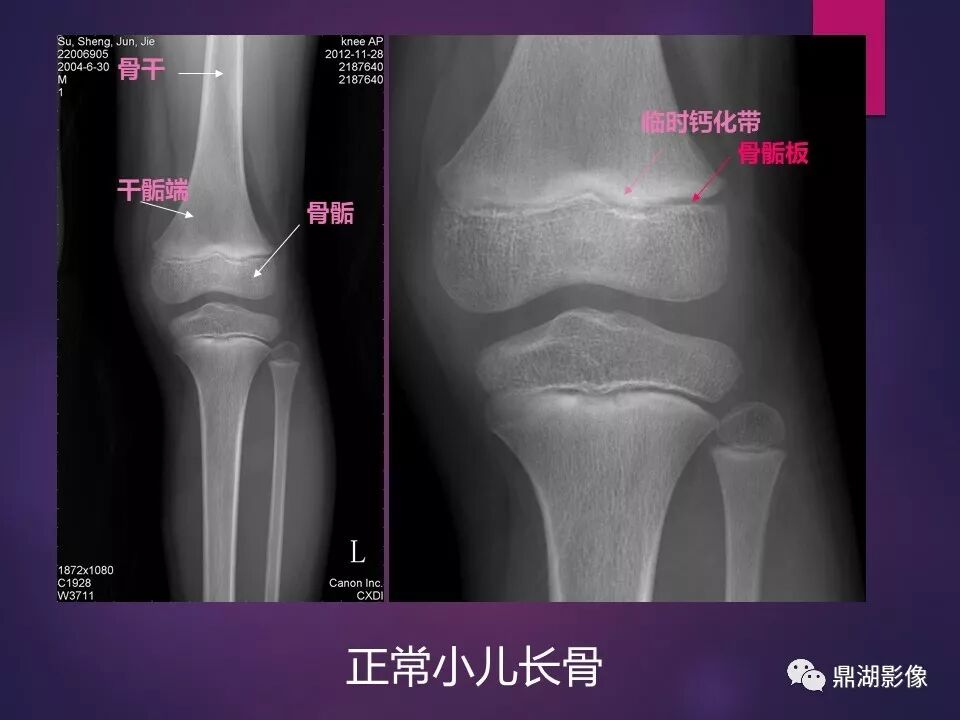

来源于:鼎湖影像 贵阳医学院医学影像系